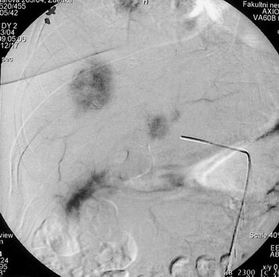

Obrázek 3 - angiografie a. hepatica před léčbou s patrnými hypervakularizovanými ložisky, které odpovídají metastázám